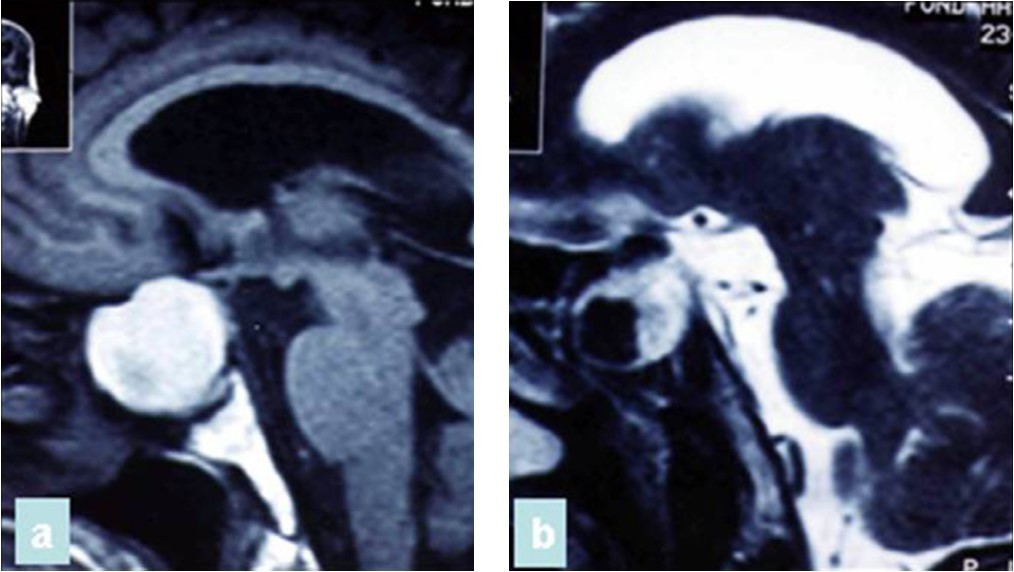

A 65 year-old man presented with progressive visual decrease and ptosis in the left eye. Neurological examination revealed paresis of the 3rd left cranial nerve. Fundoscopy revealed bilateral papillary paleness and visual acuity was: 4/10 at left; 7/10 at right. No signs of endocrine insufficiency or hypersecretion were assessed. There was no evidence of sinusitis. Chest X-ray, routine laboratory investigations and hormonal blood tests were normal. A CT scan showed a hypodense mass enlarging the sphenoid sinus and sellar region with calcification like images and bone erosion of the sellar floor (Figure 5). MRI showed a mass of 26 mm x 33 mm x 25 mm in the sphenoidal sinus ans sellar region, with hypersignal intensity in T1-weighted (Figure 6A) ans T2-weighted sequences, and hyposignal zone in T2-weighted sequences (Figure 6B). Imaging investigations were suggestive of unusual pituitary macroadenoma. The patient underwent a transnasal transsphenoidal approach for excision of the mass. A yellow-brownish gluey material with gummy debris was aspirated from the sphenoid sinus, which was completely cleaned. The sellar floor was eroded which allowed a view of the intact inflammatory dura. An intra-operative presumptive diagnosis was made of caseating granuloma (i.e tuberculosis). The post-operative course was uneventful: the patient recovered from ptosis and visual acuity improve at discharge. Mycobacterium tuberculosis could not be cultured from specimens; and cultures on Sabouraud’s medium did not isolate Aspergillus. Pathologic findings were of non invasive aspergillosis, with many septated fungal hyphae being present without tissue invasion. The patient was not given antifungal drugs because the intrasphenoidal material was completely aspirated. At 6 month and 18 months follow up, the patient had no neurological complaint. No recurrence was observed on control CT scans.

Figure 6.(a) Sagittal T1-weighted MRI showing a well circumscribed hyperintense process in the sphenoidal sinus and sellar region; (b) parasagittal T2-weighted MRI showing a regular hypointense zone into the hyperintense process which is specific to aspergillus infection and corresponds to iron accumulation